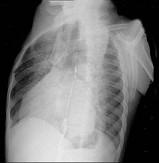

问题 56岁男性患者,劳累后心慌气促10余年,近来自觉症状加重。临床听诊,心尖区有舒张期隆隆样杂音,行胸部X检查,如图所示,你认为下列描述正确的是 ( )

选项 A、考虑三尖瓣狭窄 B、右前斜位示左心房增大,心后上缘后突压迫冲钡食管 C、左前斜位示心影向后下方突出 D、考虑二尖瓣狭窄

答案 BCD